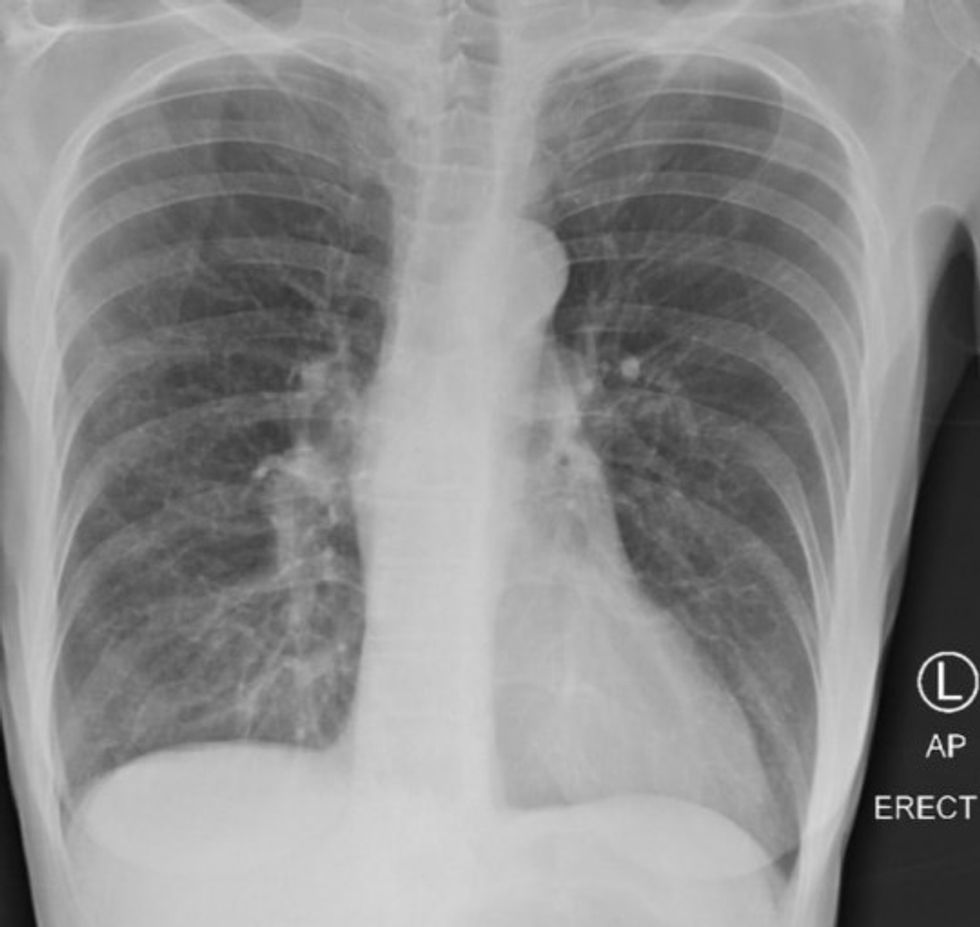

Ndërsa u shfaq në CBS DFW, mjeku ndau tre imazhe të rrezeve X: një nga një pacient i shëndetshëm, një nga një duhanpirës dhe një tjetër nga një pacient me COVID-19. /Telegrafi/

Në anën tjetër, mushkëritë e duhanpirësve janë më të mjegullt dhe tregojnë më pak dëme, madje edhe në mesin e atyre që kanë pirë duhan për vite, tha Dr Bankhead-Kendall.